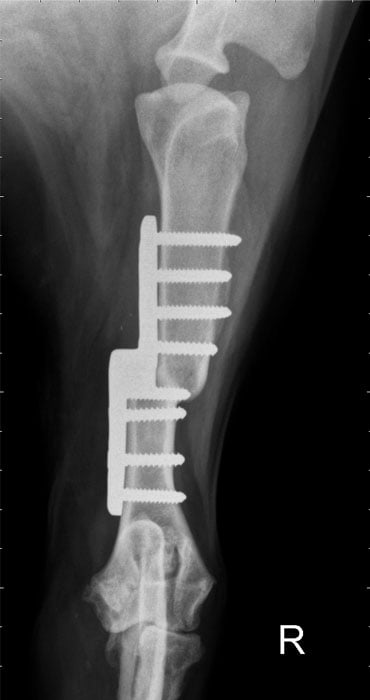

'Sliding Humeral Osteotomy' ('SHO')

Bei einigen Hunden mit fortgeschrittener ED sehen wir ebenfalls eine hochgradig sekundäre Osteoarthrose. Diese ist in der Regel verstärkt auf der Innenseite des Gelenks (medial), während auf der Außenseite (lateral) der Knorpel arthroskopisch noch als recht gut befundet werden kann. Dieser Typ von ED nennt sich mediale Kompartmenterkrankung (MCD) und kann durch eine OP - Methode namens 'SHO' chirurgisch korrigiert werden.

Die 'SHO' ist ein fortgeschrittener chirurgischer Eingriff, der nur an wenigen Kliniken weltweit durchgeführt wird. Hierzu wird der Oberarmknochen durchtrennt und in einer speziell neuen Position durch eine besondere Stufenplatte fixiert. Hierdurch wird das Gewicht der Vordergliedmaße von der erkrankten medialen Seite mehr auf die gesunde laterale Seite verlagert, ohne dabei diese zu überlasten. Durch die abnehmende Gewichtsbelastung auf das mediale Kompartment des Gelenks kann sich der Gelenkknorpel in Folge regenerieren und die Gleitfähigkeit des Gelenks verbessern.